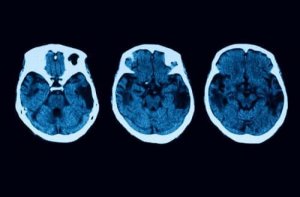

Diagnosoivat testit eivät kuitenkaan pääty tähän. Epäilyjen selvittämiseksi tehdään myös muita neurologisia kokeita, kuten magneettikuvaus ja tomografia. Jos kaikki viittaa siihen että sinulla voi olla aivokuoren atrofia, voidaan erilaisia hoitoja suositella.